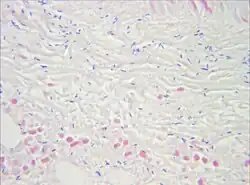

Gram stain of a muscle biopsy showing Gram-positive, rod-shaped, anaerobic, spore-forming bacteria in the infected muscle tissue: The result is highly compatible with an infection with C. perfringens.

Gram stain of a muscle biopsy showing Gram-positive, rod-shaped, anaerobic, spore-forming bacteria in the infected muscle tissue: The result is highly compatible with an infection with C. perfringens. -